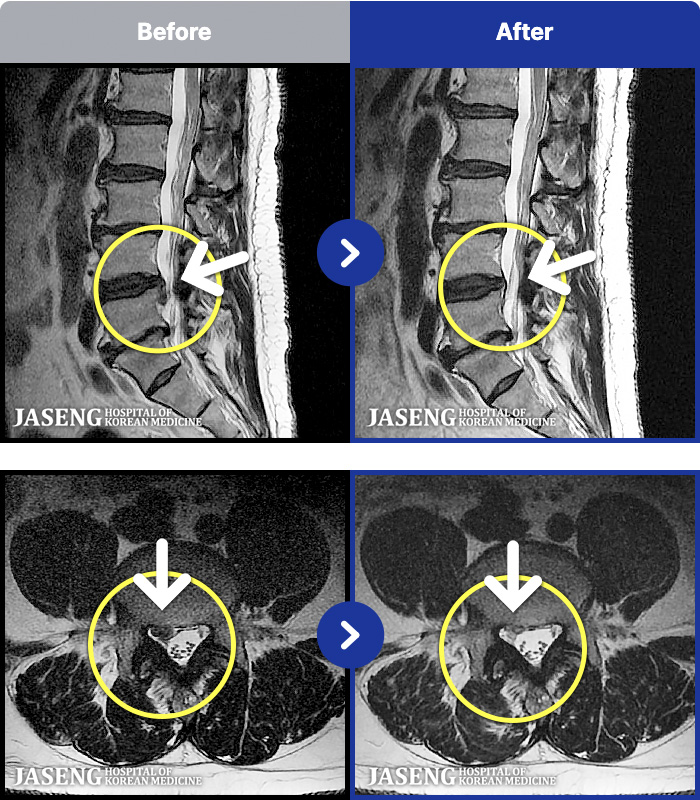

1,268 MRI ũ ʸ Ȯϼ.